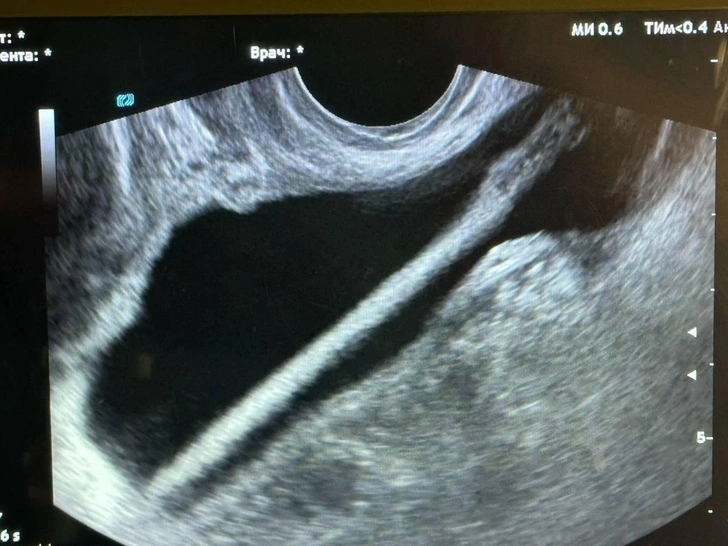

По словам Петра Сысоева, заведующего урологическим отделением стационара, после выполненного УЗИ врачи с помощью эндоскопа успешно достали инородный предмет из мочевыделительного тракта. Как в министерстве здравоохранения Московской области, сейчас пациентка уже находится дома.